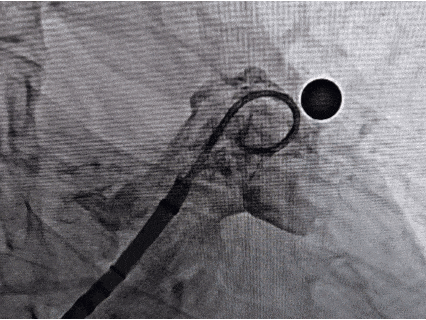

封堵器展开后DSA评估和调整

Position 位置

代表位置,即封堵器左心房侧平面正好位于左心耳口部或稍远位置

封堵器正好位于左心耳口部位置,且无露肩

Anchor 锚定

代表锚定,即牵拉试验检测封堵器稳定性

牵拉试验后封堵器位置稳定无移动